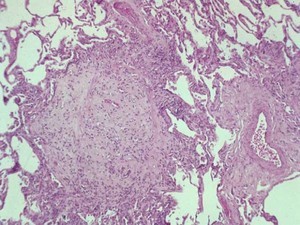

Histo:

A 50-year old man suffered from an acute respiratory viral illness 6 months ago and is currently being treated for renal failure. Now he has developed an interstitial pneumonia. Based on the histology below, what is his diagnosis?

Goodpasture syndrome–> acute pulmonary hemorrhage (below)